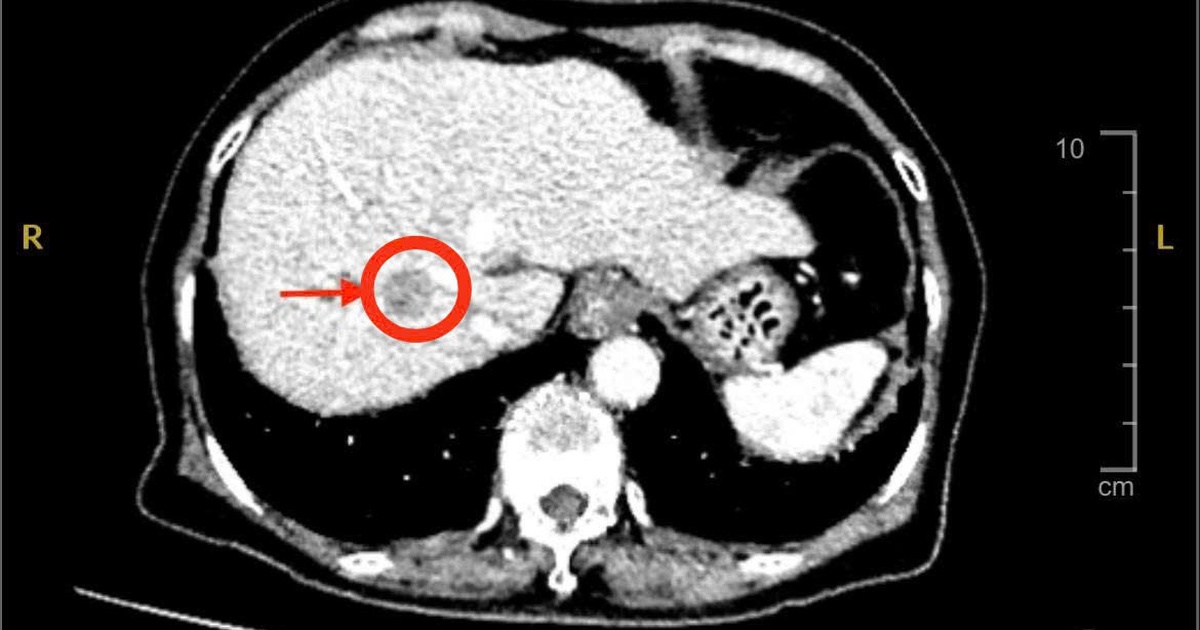

Ngày 9.11, thạc sĩ - bác sĩ chuyên khoa 2 Phan Văn Sơn, Khoa Ngoại tiêu hóa gan mật tụy, Bệnh viện đa khoa Xuyên Á cho biết, bệnh nhân được chỉ định siêu âm bụng và chụp MSCT thì phát hiện có khối u gan bên phải với kích thước khoảng 2 cm, nghĩ nhiều đến ung thư nguyên phát tế bào gan - một dạng ung thư gan phổ biến ở người có bệnh nền xơ gan, viêm gan B hoặc viêm gan C.

Trong quá trình mổ, ê kíp đã thám sát và phát hiện khối u có kích thước chỉ khoảng 2 cm. Tuy nhiên, khối u không nằm trên bề mặt mà nằm sâu trong nhu mô gan, ở vị trí rất sát mạch máu lớn ở gan. Vì thế, các bác sĩ phải sử dụng siêu âm trong mổ để xác định chính xác vị trí khối u và khống chế tất cả các mạch máu lớn nuôi gan, tránh chảy máu ồ ạt.